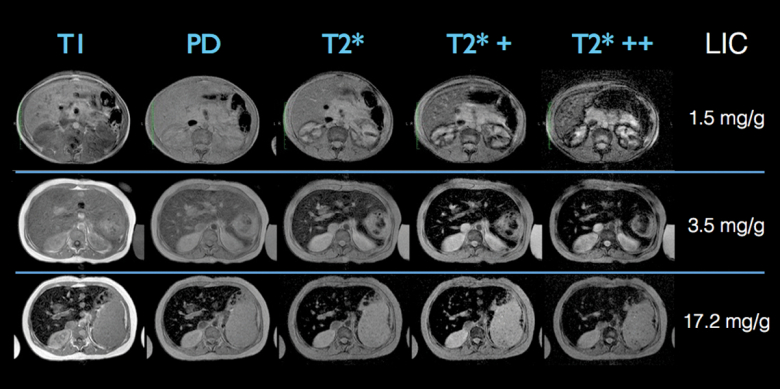

A ressonância magnética (RM) é o exame mais detalhado para estudos hepáticos e biliares. Ela possui a vantagem de não usar radiação e apresenta excelente contraste para diferenciar tipos de tecido. A RM com contraste hepato-específico (Primovist) é considerada padrão-ouro para caracterização de muitos tumores do fígado. Além disso, técnicas modernas permitem quantificar gordura e ferro, avaliando de forma precisa doenças metabólicas e hemocromatose. A ressonância também possui versões de elastografia, oferecendo uma visão tridimensional da rigidez hepática. Apesar de seus benefícios, trata-se de exame mais caro, menos disponível e que pode ser desconfortável para pessoas com claustrofobia ou implantes metálicos.